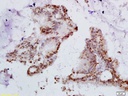

人类乳头状瘤病毒16/18 E6抗体

目录号:bs-1719R

商品规格:100ul